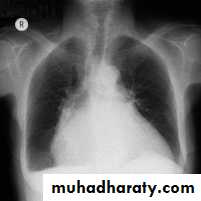

Chest X-Ray

Pulmonary edema

Heart size:

Usually normal

Cardiomegaly due to old myocardial infarctions